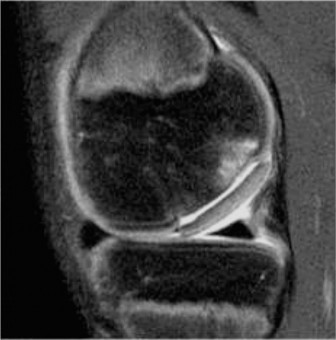

The patient responds well to a period of nonoperative management and returns to sporting activity. He is playing basketball when he has acute onset of pain, swelling, and decreased range of motion after an awkward landing. Plain radiographs are unremarkable, and a repeat MRI (Fig. 10–25) is obtained.

The correct answer is (D). The patient has an unstable lesion on MRI which is acute; therefore every attempt should be made to salvage the lesion. The ideal treatment would be fixation of the lesion although the determination for treatment cannot be made until it is examined arthroscopically. If the lesion is not deemed stable during arthroscopy, then drilling would be a reasonable option (and can be combined with fixation). If the fragment is nonviable, microfracture would be a reasonable option to stimulate fibrocartilage formation as long as the donor site is not too large. Fragment removal and chondroplasty is not ideal for a young patient; particularly one who is engaged in sporting activities. Every attempt should be made to salvage the lesion and/or stimulate new cartilage formation if the fragment is unsalvageable. The lesion is shown arthroscopically (Fig. 10–26). The appropriate treatment option is: